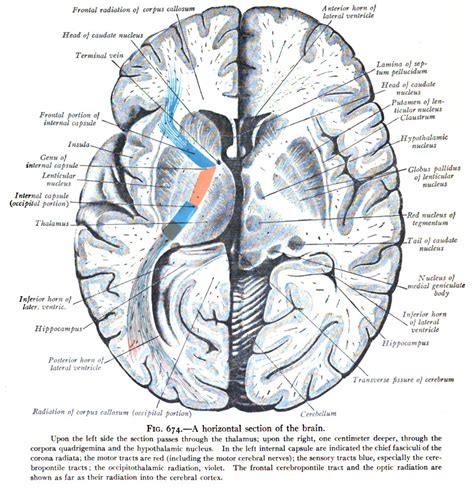

The internal capsule is a V-shaped structure composed of white matter tracts, situated between the thalamus and the caudate nucleus medially, and the lentiform nucleus laterally. Because it acts as a funnel for thousands of nerve fibers, it is categorized into distinct segments, each carrying specific types of information. From a structural perspective, these segments are crucial for clinical localization during diagnostic imaging, such as an MRI.

The structure is anatomically divided into the following key components:

• Anterior Limb: Situated between the head of the caudate nucleus and the lentiform nucleus, this area primarily contains frontopontine fibers and thalamocortical fibers.

• Genu (The Knee): This is the bend in the V-shape, where the anterior and posterior limbs meet. It is home to the corticobulbar tract, which is essential for controlling cranial nerves.

• Posterior Limb: Located between the thalamus and the lentiform nucleus, this segment is highly significant as it contains the main corticospinal tract, which manages voluntary motor movements of the body.

• Retrolenticular and Sublenticular Parts: These posterior-most sections carry optic and auditory radiations, relaying visual and auditory information to the visual and auditory cortices, respectively.